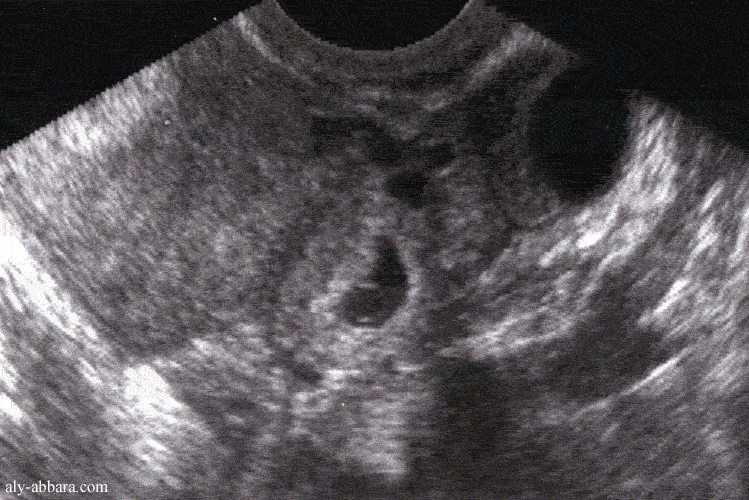

3. La grossesse extra-utérine, ou grossesse ectopique, est une grossesse se développant hors de l'utérus. La très grande majorité des grossesses extra-utérines sont des grossesses dans la trompe de Fallope ou grossesses tubaires. La grossesse extra-utérine est une urgence chirurgicale dans sa forme rompue. Son diagnostic est de plus en plus précoce permettant d'éviter sa rupture et la mise en jeu du pronostic vital et permettant un traitement non chirurgical sous certaines conditions strictes.